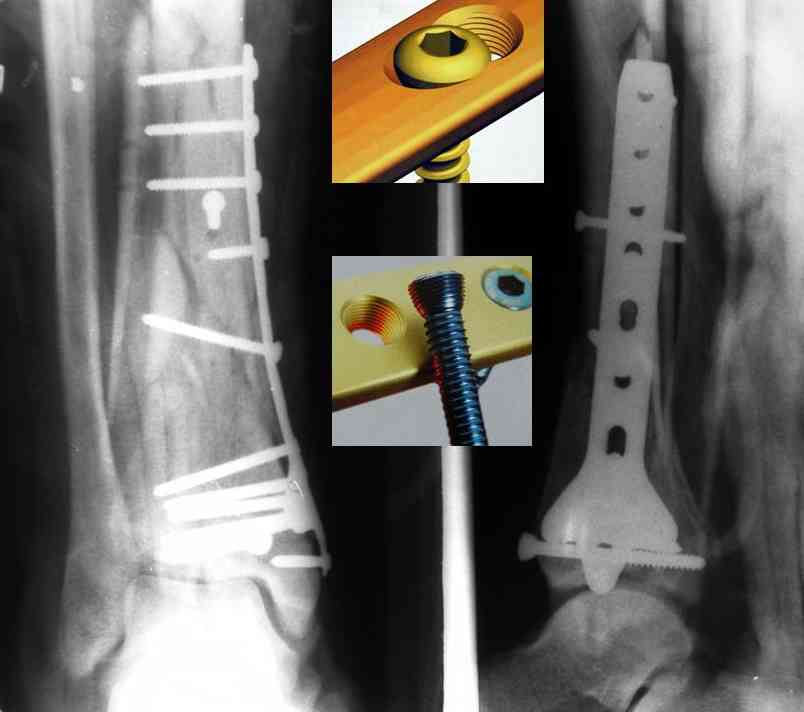

Дрягин В. 04 Январь 2007, 13:28

Кстати, при переломах переднего края по классификации АО В-3 при переломах пилона пластина укладывается по передней поверхности. Она достаточно тонкая и эластичная, не надо этого бояться. Посылаю три снимка.